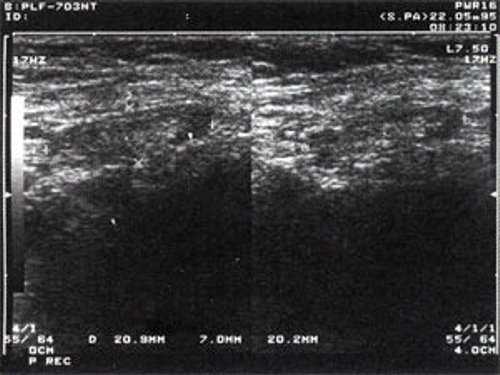

Практически во всех случаях дифференцировали лимфатический узел Кютнера (югулодигастральный), расположенный на границе средней и верхней трети шеи. Выявляемые лимфатические узлы имели размеры от 0,5 х 0,2 см до 2,3 х 0,8 см. УЗ-оценку производили после полипозиционного осмотра и нахождения самой длинной горизонтальной оси, что и принимали за максимальный поперечный диаметр. Большая часть лимфатических узлов (187) имели овальную форму с соотношением поперечного/переднезаднего более 1 (рис. 1 - 3). Тенденцию к округлению имели 30 лимфатических узлов, соотношение поперечного/переднезаднего приближалось к 1.

Рис. 2. Эхографическое изображение непальпируемого югулярного лимфатического узла на фоне остаточных явлений после перенесенного фарингита.